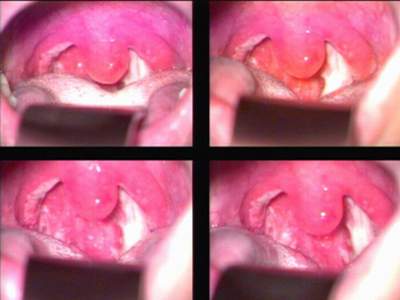

| Hình ảnh họng bị viêm. |

Khi khám sẽ thấy toàn bộ niêm mạc họng đỏ rực. Màn hầu, trụ trước, trụ sau và thành sau họng phù nề, đỏ, xuất tiết. Hai amiđan sưng to, nếu viêm tái phát thì amiđan thường có hốc, có thể có mủ hoặc bựa trắng như nước cháo phủ trên bề mặt hoặc miệng các hốc amiđan. Xét nghiệm công thức máu sẽ thấy bạch cầu tăng cao, tốc độ máu lắng tăng, chỉ số CRP (C Reaction Protein) dương tính. Xét nghiệm nhày họng, bằng phương pháp nhuộm đơn thấy nhiều tế bào bạch cầu, vi khuẩn (trực khuẩn hoặc cầu khuẩn). Nhuộm bằng phương pháp gram có thể thấy cầu khuẩn gram dương (xếp đôi, hoặc thành đám hoặc đứng riêng rẽ) hoặc thấy cả xoắn khuẩn Vincent. Nếu có điều kiện nuôi cấy chất nhày họng sẽ xác định được loại vi khuẩn gây viêm họng cấp, trên cơ sở đó thực hiện kháng sinh đồ để chọn kháng sinh thích hợp cho việc điều trị.